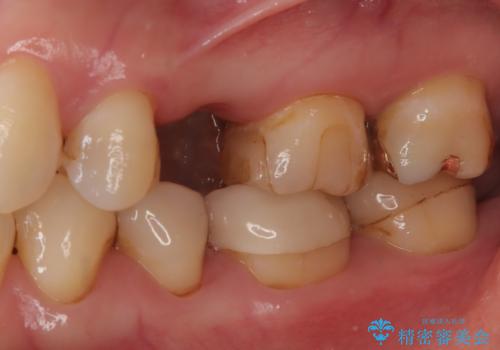

- 根管治療をしている歯が破折し、抜歯となってしまいました。

抜歯した部位に対して、はじめに可撤性部分義歯,ブリッジ、インプラントによる治療方法とそれぞれの利点と欠点について説明を行った結果、インプラント治療を希望されました。さらに、インプラント治療の術前・術後口腔内管理の重要性、手術内容,費用などを説明し、十分なインフォームド・コンセントを得たうえで治療を開始しました。